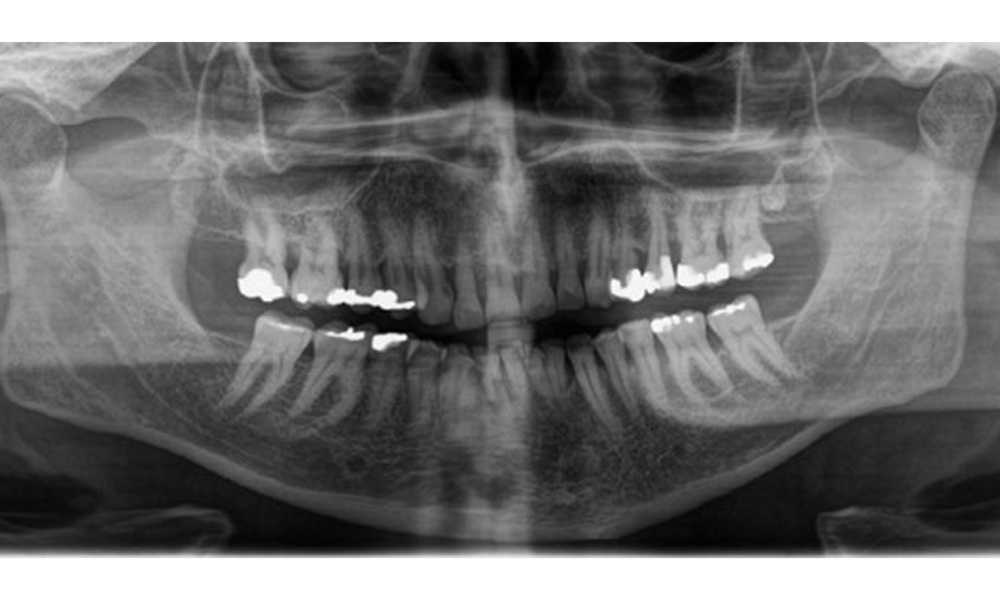

Es zeigt sich ein vollbezahntes Erwachsenengebiss mit einem generalisiertem Knochenabbau zwischen 20-50% und multiplen vertikalen Knocheneinbrüchen. Radiologisch ist keine kariöse Läsion sichtbar. (Abb. 7)

Panoramaschichtaufnahme zur Darstellung des generalisierten radiologischen Knochenabbaus mit multiplen vertikalen Defekten zwischen 20-50%. © Dr. R. Krapf

Abb. 7 Panoramaschichtaufnahme zur Darstellung des generalisierten radiologischen Knochenabbaus mit multiplen vertikalen Defekten zwischen 20-50%. © Dr. R. Krapf